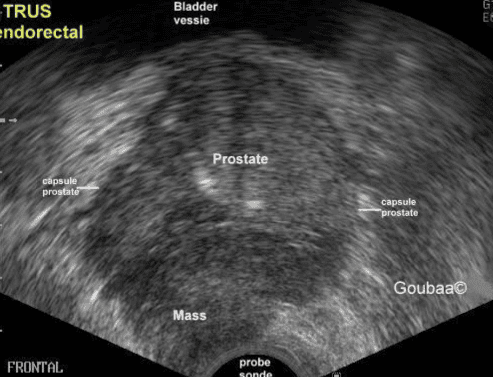

• Siêu âm: Nếu các xét nghiệm khác làm tăng nghi ngờ mắc bệnh ung thư tiền liệt tuyến, bác sĩ có thể sử dụng siêu âm để tiếp tục đánh giá tuyến tiền liệt. Thăm dò này sử dụng sóng âm thanh để tạo ra hình ảnh của tuyến tiền liệt.

Hình ảnh siêu âm ung thư tiền liệt tuyến